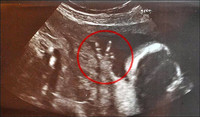

Ecografía 4D, ¿qué tener en cuenta antes de contratarla?

EmbarazoEn entradas anteriores hemos hablado de la gran revolución que ha supuesto la ecografía para los controles prenatales y la novedad de la ecografía 4D, una ecografía tridimensional que añade el componente de poder ver al bebé en...